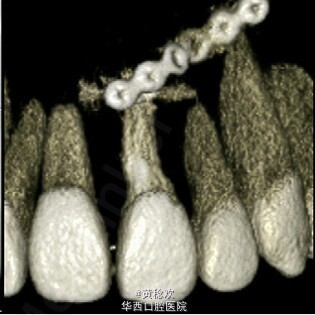

牙齿脱位对牙周膜、牙槽骨、牙龈、牙髓和牙骨质造成严重损害。脱位牙再植后经常伴有牙骨粘连等并发症。牙骨粘连指的是局部牙骨质和周围牙槽骨融合,多起因为牙齿正在萌出过程中或萌出后受到机械性、温度或者代谢产物刺激,对牙周膜造成损伤,好发于恒切牙。 牙骨粘连可通过临床和放射片检查诊断。临床检查包括低咬合状态、叩诊和松动度测试,最明显的特征是即便该牙施加正畸牵引力后也无法移动。整个牙的牙骨粘连可以通过放射片显示,其特征为无明显的牙周膜影响。但是如果该牙只有颊侧或者舌侧粘连,放射片上很难判断。近年来,CBCT的引入,可以逐渐将放射检查视野拓宽到3D层面,增强了对骨牙粘连的准确性。治疗骨牙粘连的方案包括:拔除、截冠、修复、手术半脱位、骨切开术和牵张成骨术等。